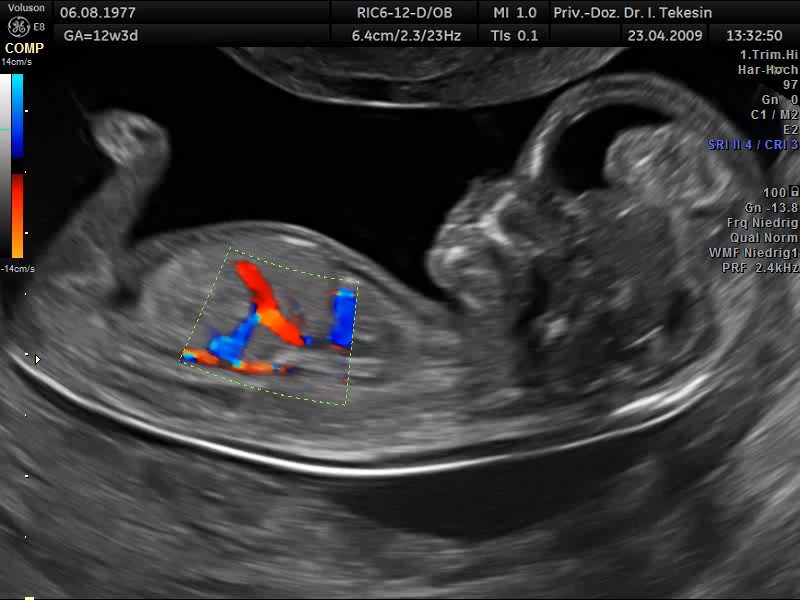

Ein weiterer Bestandteil der weiterführenden Ultraschall-Diagnostik ist die Beurteilung des kindlichen Herzens und der großen Blutgefäße, die fetale Echokardiographie. Dabei untersuchen wir die Lage, Größe und Symmetrie des Herzens, Anatomie der Herzstrukturen, Funktion der Herzklappen, Herzfrequenz und die Lage der großen Gefäße. Mit Hilfe der farbkodierten Doppler-Sonographie des Herzens werden weitere Details untersucht: die Funktion der Herzkammern, Herzscheidewände, Blutflüsse im Herzen und Blutflüsse in den großen Gefäßen.

Dopplersonographie

Auch das Durchblutungsverhalten in der Nabelschur und in den Gebärmuttergefäßen wird mit Hilfe des Doppler-Ultraschalls dargestellt. Diese Untersuchung ist eine ergänzende Untersuchung im Rahmen der US-Feindiagnostik und ermöglicht eine Beurteilung des Blutflusses in den kindlichen und mütterlichen Gefäßen mittels einer speziellen Technik. Bei dieser Untersuchung wird die Blutströmung farbig und akustisch dargestellt. Die Geräusche, die man während der Untersuchung hören kann, entstehen durch technische Effekte (Doppler-Effekt), welche der Untersucher und die werdende Eltern hören können, jedoch nicht das ungeborene Kind.

Die Beurteilung des Blutflusses in den kindlichen Gefäßen (Nabelschnurarterie [A. umbilicalis], A. cerebri media und Ductus venosus) ermöglicht eine Aussage zur Versorgung des ungeborenen Kindes. Die Doppleruntersuchung kann in unterschiedlichen Zeitpunkten der Schwangerschaft durchgeführt werden.

Fetale Zirkulation in der 13. SSW

Darstellung des DV in der 13. SSW mittels Farb-Doppler